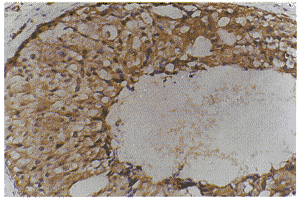

图3 p21ras阳性表达的乳腺癌

(细胞浆内可见棕黄色染色颗粒,SP×400)

图4 nm23阳性表达的乳腺癌

nm23、p21ras、VEGF免疫组化染色后细胞浆内有棕黄色染色颗粒为表达阳性,阴性为全部癌细胞无特异性染色。ER免疫组化染色后细胞核内有棕黄色染色颗粒为阳性细胞,阳性细胞占全部癌细胞50%以上为表达阳性(图~4)。nm23、p21ras、VEGF和ER的阳性表达率在乳腺癌组高于良性病变组,两者间差异有显著意义,P<0.05(表1)。